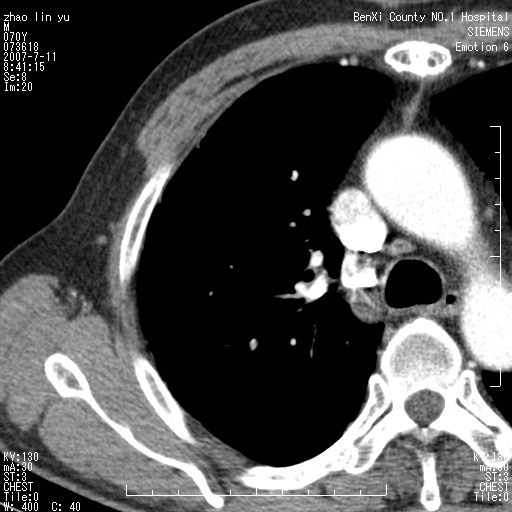

以下是引用王靖旗在2007-7-10 17:12:00的发言:[br] 男、70、咳嗽两个月,半年前换瓣手术,胸片未见异常,于昨天行x片发现右肺上野大片影,行ct扫描,这里是减薄图像,余肺正常。明天晚上会有增强扫描片,到时我会上传。[br][br] 冠状位请大家细看,应该是有意义的,[br][br] 请大家先看平扫发表意见。[br][br]

以下是引用zhangzhongshou在2007-7-10 21:43:00的发言:[br]右肺上叶周围型肺癌,以孤立型细支气管肺泡癌可能性大。